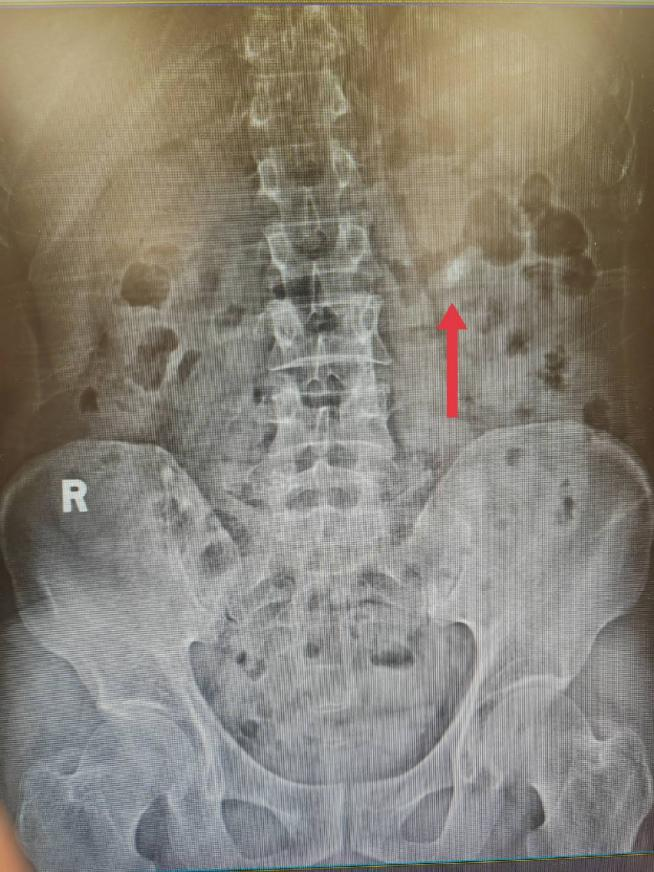

术前影像学检查: